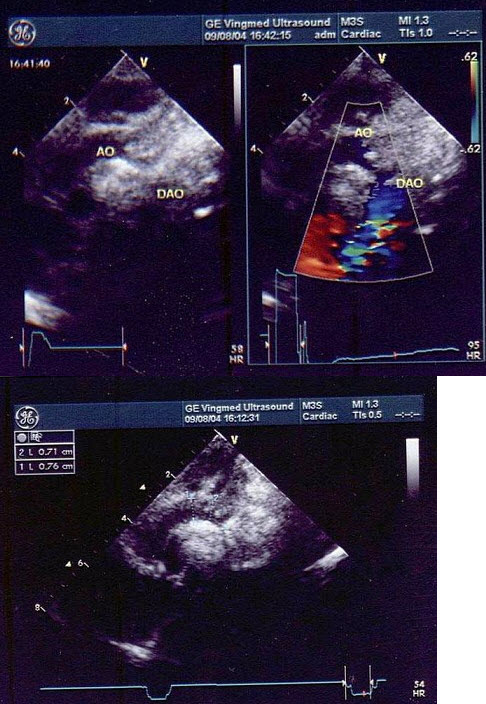

A.混响

B.部分容积效应

C.旁瓣效应

D.折射声影

E.声速差异伪像

D.左心衰竭

E.二尖瓣关闭不全

52、单项选择题 为了调节灰阶超声仪器的工作条件达到最佳状况,下列哪项内容不重要()

A.提高空间分辨力

B.提高时间分辨力

C.选择适当的图像前后处理及动态范围

D.调节M型的扫描速度

E.选择适宜的灰阶数